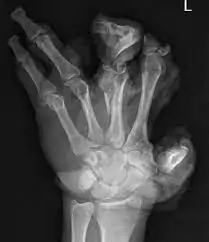

Accidents involving blasts, gunshots, and cracker explosions can lead to severe hand injuries, often resulting in mutilation. These injuries require specialized medical attention and precise management.

Managing a mutilated hand due to blast injuries, considering factors like limb ischemia and amputation, is a complex process that demands specialized skills and expertise. If there’s limb ischemia or partial amputation, the possibility of reimplantation is considered. The amputated part should be carefully transported in a plastic bag with ice at an ideal temperature of 4 degrees Celsius. Once the patient’s overall condition stabilizes and other critical injuries are addressed, the hand injury is evaluated.

Reimplantation is not possible or feasible in most of the cases of hand blast injuries even if the part is brought well preserved as there is injury to the vital structures at multiple levels within the part or the part is damaged beyond recognition or is in shreds. In a few isolated cases, where the part is well preserved relatively, reimplantation can be attempted with guarded consent.

Diagnosis involves clinical evaluation, imaging studies like X-rays, CT scans, or MRIs to assess internal damage, and specialized tests to evaluate nerve or vascular injuries.